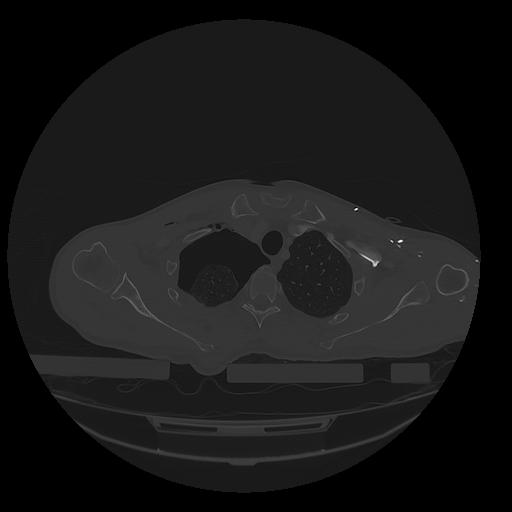

31 PULMON,CE,Vol,1.0,PULMON,,